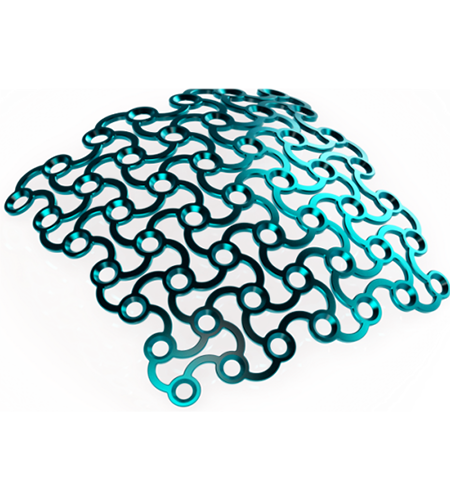

Patient-specific implants are designed and produced according to patient-derived CT data for excellent reconstructive results. Our main products are patient-specific implants for the brain- and face-skull areas. These patient-specific implants can, for example, become a necessity after trauma, tumour surgeries, surgery accesses. This new procedure allows us to create implants that are custom-made for every patient.

Implant material

- Commercially pure titanium

- Ultra-high strength

- Excellent biocompatibility

- Radiopaque

- Autoclavable – withstands repeated sterilization

- Requires the use plates and screws are used to attach the patient specific implant to native bone.